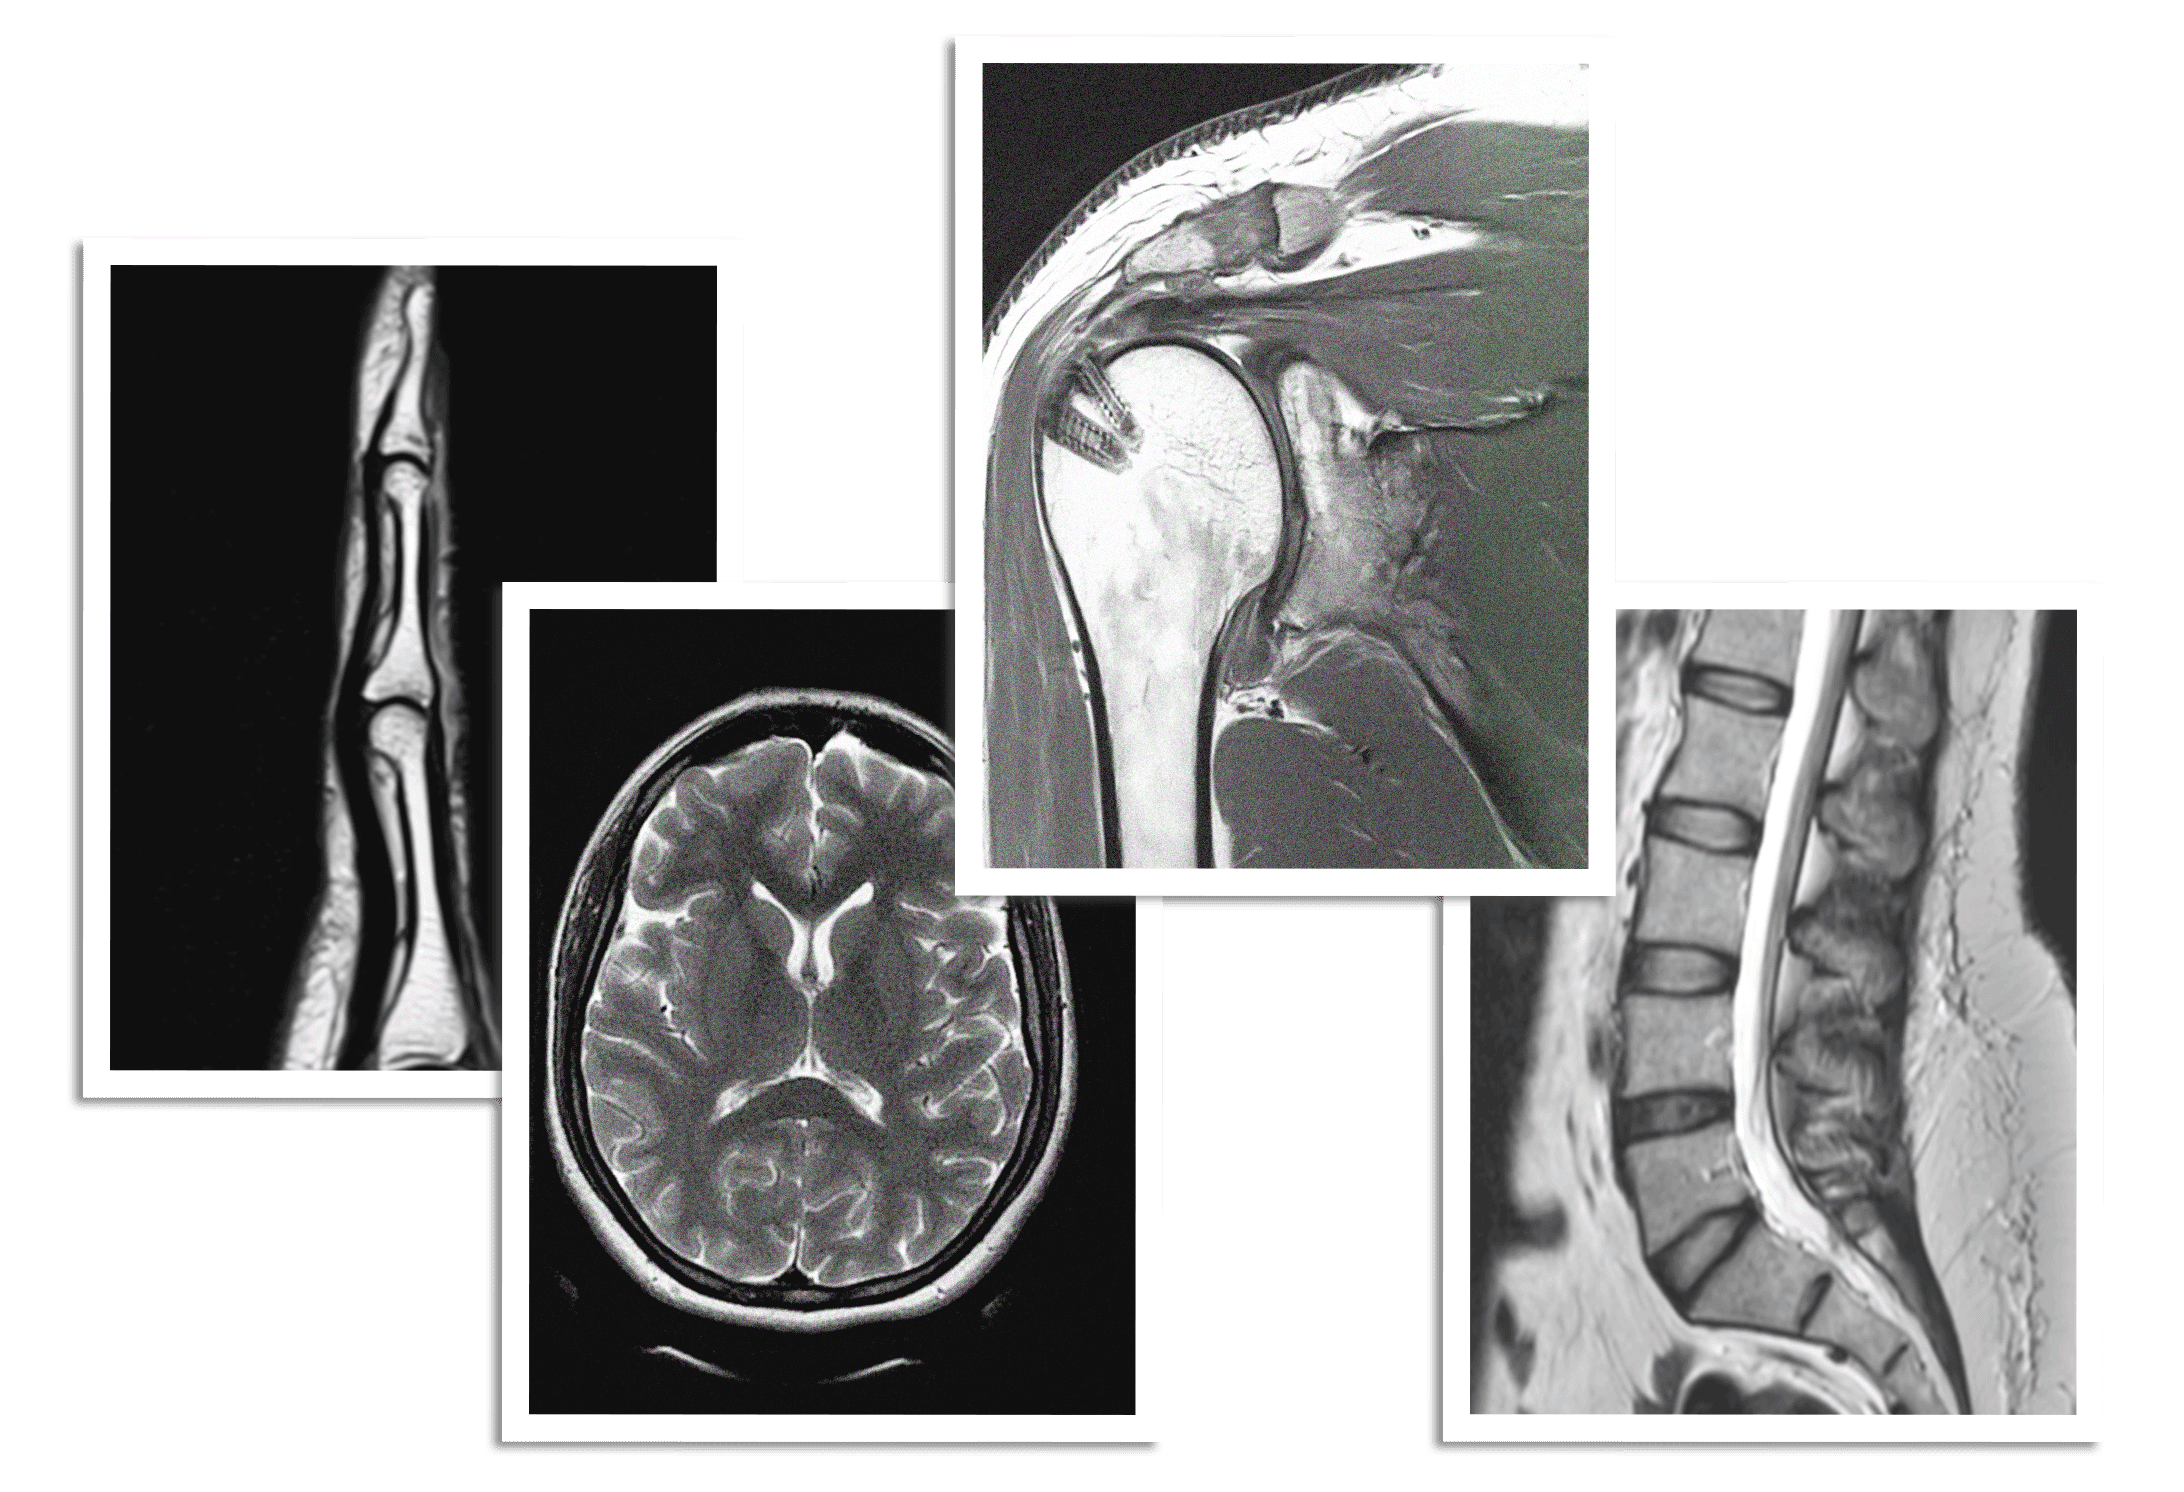

Dedicated subspecialty reporting by our team of radiologists.

EVAA Radiology is a specialized center committed to excellence in teleradiology, advanced imaging, as well as teaching the newer generation of radiologists. Led by nationally and internationally renowned Dr. Chaitali Parekh, Consultant Musculoskeletal diagnostic and intervention radiologist, we combine precision, innovation, and education to deliver trusted diagnostic and intervention excellence.

Diagnosis and management of sports injuries, joint pain and back pain through imaging and injections.

Image guided MSK injections & bone, soft tissue and synovial biopsies.